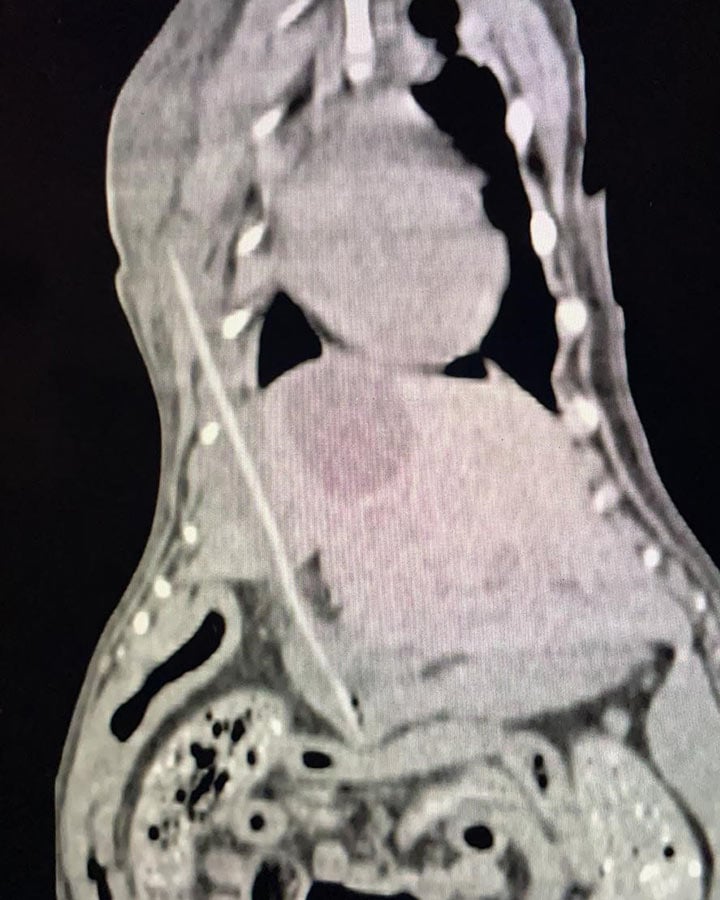

To the teams’ surprise, the CT scan showed an entire kebab stick going all the way through her stomach and liver! As she had no clinical signs of a foreign body before the scan, both the team and Kallie’s owners couldn’t believe their eyes. The fact Kallie was still wagging her tail throughout all of this was remarkable.

She was immediately booked in for surgery at Medivet 24 Hour Alder and we’re pleased to say the kebab stick was successfully removed and Kallie is expected to make a full recovery.